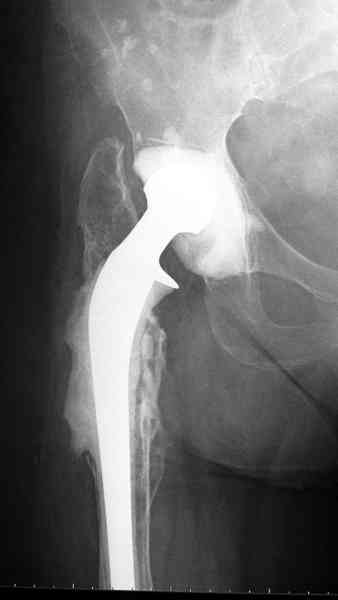

Представляю вашему вниманию снимки (прошу прошения за качество снимков) больной 48 лет с ревматоидным артритом, которой был сделан тотальный эндопротез справа,

контрольный снимок сделали только на 21день после операции (№1) и с интервалом 5 дней второй снимок (№2)

Судя по всему, произошел раскол наружной стенки бедра и ножка находится вне костного канала. В таком случае

решение одно - удаление ножки и установка новой в расчете на дистальную фиксацию. Конктреную модель подсказать тяжело из-за низкого качества Р-грамм.